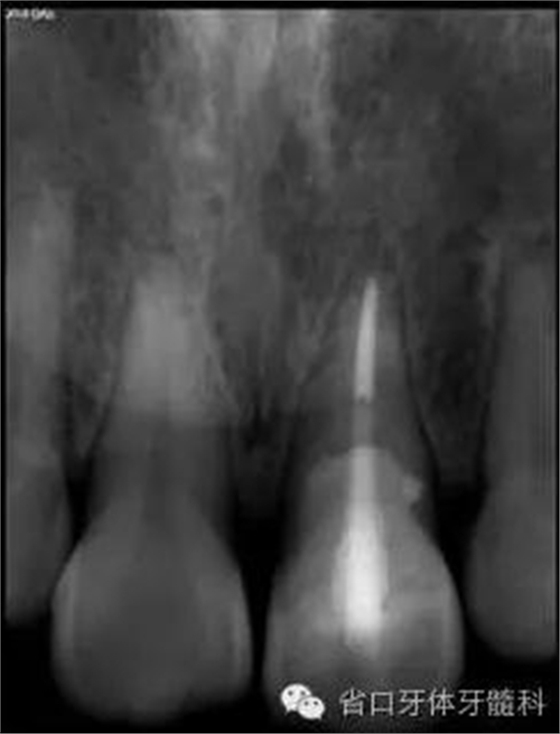

圖8. 21/行根管治療術,保留根尖約5mm的根充物,根中上段預留空間以預備纖維樁道。

圖17. 術后X線片